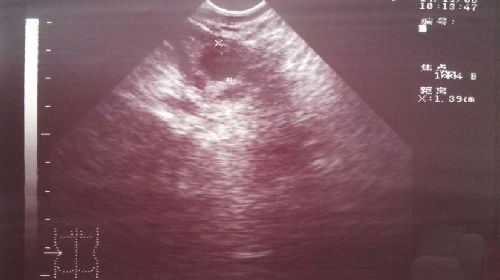

卵泡监测方法

卵泡监测方法就是阴道B超检测,如果想要更加准确的判断卵泡发育程度、排卵日和黄体功能如何的话,建议配合基础体温检查,每次检查时间很短,不用担心花费太多时间。